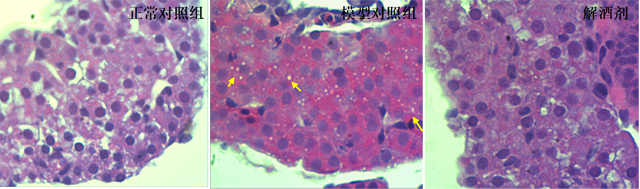

图2. 肝脏病理切片

黄色箭头指向脂肪颗粒

从病理切片中也能看出来,酒精性脂肪肝斑马鱼的肝脏有很多脂肪颗粒,而服用解酒剂组的肝脏情况与未摄入酒精的正常对照组都没有出现类似的脂肪颗粒。